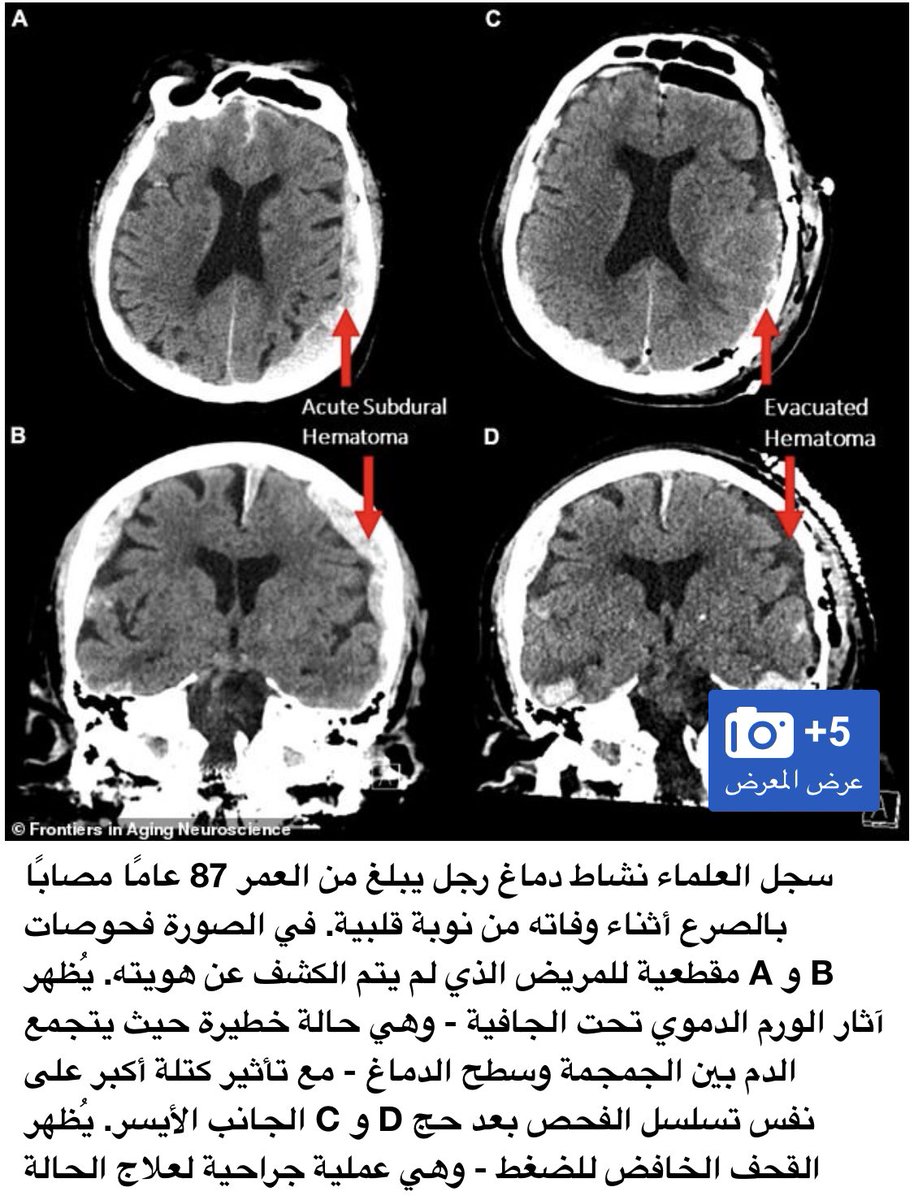

قام العلماء لاول مرة بتسجيل نشاط الدماغ الإنسان عند وفاته حيث أجريت لمريض كبير بالسن عمره87 ومصاب بمرض الصرع،قاموا بوضع جهاز تخطيط كهربائي وسجلوا نشاط الدماغ لمدة 15دقيقة،واكتشفوا العلماء شي غريب وعلموا من خلاله ماذا يشاهد الانسان عند حضور أجله.

لاحظوا العلماء ان نشاط كبير بموجات غاما بالدماغ والتي ترتبط بعمليات مثل الحلم والتأمل واسترجاع الذاكرة اي بمعنى ان الانسان يشاهد شريط حياته بشكل كامل قبل رحيله وتكون بعملية تسمى استدعاء الحياة،ونلاحظ ان الاشخاص الذين تتوقف قلوبهم يشاهدون اشياء غريبة من كائنات يشع منه النور.